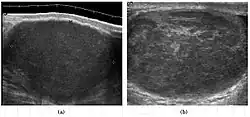

Seminoma is the most common tumor type in cryptorchid testes. The risk of developing a seminoma is increased in patients with cryptorchidism, even after orchiopexy. There is an increased incidence of malignancy developing in the contralateral testis too, hence sonography is sometimes used to screen for an occult tumor in the remaining testis. On US images, seminomas are generally uniformly hypoechoic, larger tumors may be more heterogeneous [Fig. 3]. Seminomas are usually confined by the tunica albuginea and rarely extend to peritesticular structures. Lymphatic spread to retroperitoneal lymph nodes and hematogenous metastases to lung, brain, or both are evident in about 25% of patients at the time of presentation.